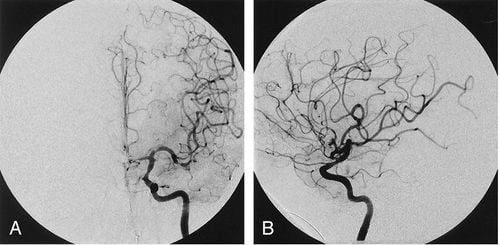

- Ghi hình và chụp phim: chụp seri với máy X-quang số hóa xóa nền, tập trung vào vùng quai động mạch chủ và các mạch máu lớn xuất phát từ đây (động mạch thân cánh tay đầu, động mạch cảnh trái, động mạch dưới đòn). Để hiện rõ quai động mạch chủ và các nhánh mạch tách ra từ quai thường chụp chếch trước trái.

Chụp động mạch chủ ngực

Tiến hành kỹ thuật tương tự như trên, nhưng đầu ống thông được kéo lùi hơn và khi ghi hình tập trung vào vùng động mạch chủ ngực: có thể chụp chếch trước trái hoặc chụp thẳng.